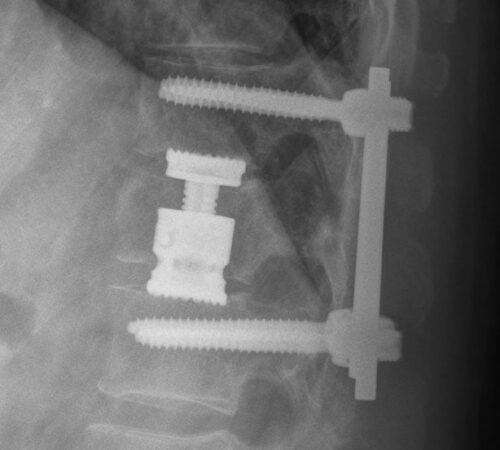

• Tříštivá zlomenina obratle T12 po kombinovaném ošetření vnitřním fixátorem v rozsahu T11-L1

Jednotlivé procedury se při operačním výkonu prolínají a fungují společně. Pro zajištění primární pooperační stability ze zadního přístupu používáme v krční i torakolumbální oblasti vnitřní fixátory. Jejich součástí jsou šrouby případně háky a spojovací tyče překlenující poraněný páteřní segment. Z předního přístupu jsou nejčastěji aplikovány kostní štěpy nebo klece přemostěné dlahou v krční oblasti, expandibilní klece a fixátory v torakolumbální oblasti. Všechny fixační prvky jsou vyrobeny ze slitiny titanu, která omezuje negativní stíny na vyšetření CT a jsou MR kompatibilní. Pro dosažení trvalé kostní stability používáme přemostění poraněného obratle nebo obratlů kostními štěpy z lopaty kosti kyčelní nebo syntetickou náhradu (trikalciumfosfát, hydroxiapatit).